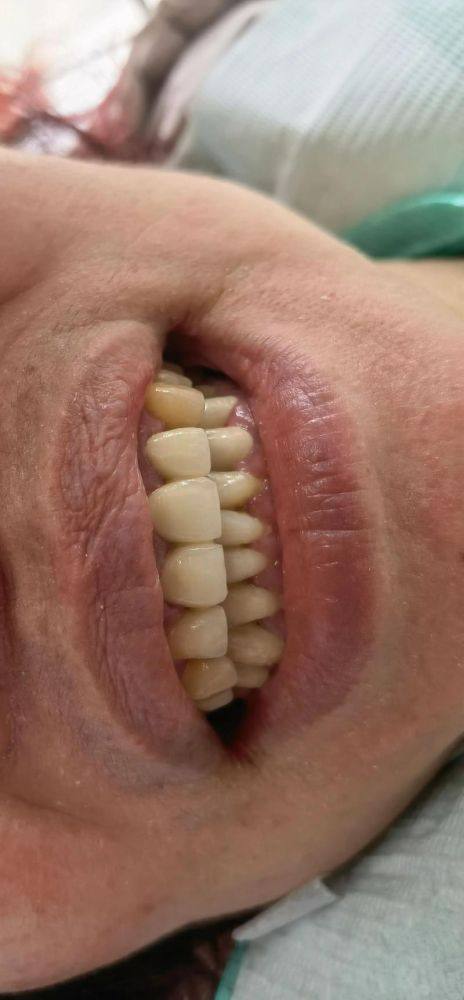

众多患者对大同金冠口腔门诊部给出了高度评价。有患者表示“我在金冠口腔门诊部做了种植牙手术,医生的手法非常优质,手术过程轻松痛感低。术后修复得特别不错,现在我的牙齿看起来非常整齐,自信心也提高了不少。医院的服务也非常周到,让我感到非常满意”。还有患者提到“孩子之前一直特别害怕看牙医,在这里医生特别耐心细致,孩子一点都不怕了”。从各方面来看,大同金冠口腔门诊部技术靠谱,服务贴心,环境舒适,收费合理,并非大家所担心的“坑”。它凭借专精的医疗团队、精良的设备、丰富的项目和优质的服务,值得大家信赖,是口腔健康的优质选择。